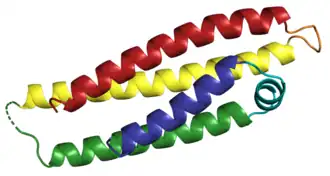

Dementia with Lewy bodies can be classified in other ways. The atypical parkinsonian syndromes include DLB, along with other conditions.[12] Also, DLB is a synucleinopathy, meaning that it is characterized by abnormal deposits of alpha-synuclein protein in the brain. The synucleinopathies include Parkinson's disease, multiple system atrophy, and other rarer conditions.[13]

DLB is characterized by the development of abnormal collections of alpha-synuclein protein within diseased brain neurons, manifesting as Lewy bodies and Lewy neurites.[86] When these clumps of protein form, neurons function less optimally and eventually die.[18] Neuronal loss in DLB leads to profound dopamine dysfunction[94] and marked cholinergic pathology;[95] other neurotransmitters might be affected, but less is known about them.[96] Damage in the brain is widespread, and affects many domains of functioning.[18][a]

The precise mechanisms contributing to DLB are not well understood and are a matter of some controversy.[100] The role of alpha-synuclein deposits is unclear, because individuals with no signs of DLB have been found on autopsy to have advanced alpha-synuclein pathology.[86] The relationship between Lewy pathology and widespread cell death is contentious.[100] It is not known if the pathology spreads between cells or follows another pattern.[101] The mechanisms that contribute to cell death, how the disease advances through the brain, and the timing of cognitive decline are all poorly understood.[100] There is no model to account for the specific neurons and brain regions that are affected.[100]

Two 1997 discoveries highlighted the importance of Lewy body inclusions in neurodegenerative processes: a mutation in the SNCA gene that encodes the alpha-synuclein protein was found in kindreds with Parkinson's disease, and Lewy bodies and neurites were found to be immunoreactive for alpha-synuclein.[229] Thus, alpha-synuclein aggregation was established as the primary building block of the synucleinopathies.[229]